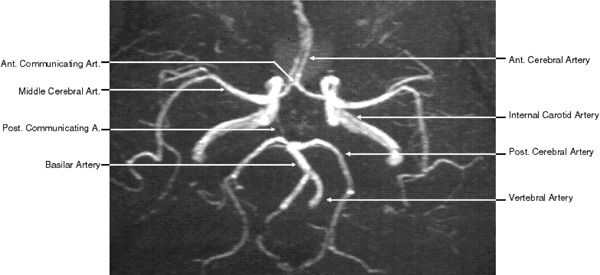

MRA

Flow effect produces phase shift artifacts on standard MRI. These artifacts were recognized in the early 1950s and were considered as nuisances, with efforts made to minimize these troublesome manifestations. However, with the development of newer, faster imaging techniques, the signal change resulting from physiologic flow could be exploited for imaging purposes in the form of MRA. These flow-induced changes in the MR signal use the motion itself as the agent of contrast, thus avoiding the need for an invasive procedure and the use of contrast.

The motion during either excitation or sampling results in two types of corresponding effects on the MR signal of moving spins: first, the wash-in/out or “flight” of spins relative to the timing and placement of the pulse producing the time of flight (TOF) effect, and second, spins moving during the application of, and in the direction of, an imaging gradient producing a shift in signal phase dependent of the type of flow (e.g., constant velocity, turbulence) and gradient in the flow direction (spin phase phenomenon).36–38 These two flow-induced variations in the MR signal form the basis for the different MRA techniques for identifying and quantifying flow.

There are many techniques to produce MRA. The one that has gained the widest use is the TOF MRA. This technique takes advantage of the TOF and especially an effect called flow-related enhancement (FRE). Repetitive radiofrequency signals are applied in quick succession. This can prevent any meaningful relaxation of stationary protons between radiofrequency excitations within the field of interest. Under these circumstances, stationary protons emit only weak signals. On the other hand, moving protons (in a bulk of flowing blood) entering the field between excitation are completely relaxed and are exposed to fewer pulses and therefore emit a greater signal than the surrounding stationary protons. With this technique, the signal from background static material is suppressed, producing relative enhancement of the signal from flowing blood.

With 2D TOF, multiple thin imaging slices are acquired with a flow-compensated gradient-echo sequence. Slice thickness is limited to 1.5 mm. These images can then be combined by using a technique of reconstruction such as maximum intensity projection (MIP) to obtain a 3D image of the vessels analogous to conventional angiography (Fig. 11). The 2D TOF MRA technique is robust and relatively fast; it may be adequate for screening, but it is less accurate for gauging the degree of stenoses.

Fig. 11. Two-dimensional time-of-flight magnetic resonance angiography of the circle of Willis (superior view).

With 3D TOF, a volume of images is obtained simultaneously by phase encoding in the slice-select direction. The signal is acquired from an entire slab of tissue, up to 6 cm thick. An angiographic appearance can be generated using MIP, as is done with 2D TOF. Several 3D TOF volumes can be combined to visualize longer segments of vessels. The slab can also be subdivided into many slices, source images, or partitions, each 1 mm or less thick. The 3D TOF offers proportionately greater SNR compared with the thin 2D TOF slice. Thus, the advantages of 3D TOF MRA techniques (compared with 2D TOF) are better SNR and better spatial resolution in the slice-select direction.39 3D TOF MRA allows greater spatial resolution in the slice-select direction relative to 2D TOF; however, with thick volumes and slow-flowing blood, loss of signal is seen with the 3D TOF method. The disadvantage of 3D TOF is the phenomenon of saturation. Maximum flow-related enhancement occurs when the fresh spins enter the slab fully magnetized or unsaturated. After being exposed to multiple 90-degree radiofrequency pulses as the spins traverse the slab of tissue, the magnetization is used up and the spins are said to be saturated, at which point no additional signal can be elicited. Visualization of vessels deeper into the slab is thus limited. Saturation limits the total 3D TOF slab thickness to approximately 6 cm for blood flowing at the velocity of vessels in the circle of Willis.

A technique called multiple overlapping thin slab acquisitions (MOTSA) is a hybrid that takes advantage of both positive features.40 With MOTSA, a number of relatively thin 3D TOF slabs are pasted together like so many 2D TOF slices, providing unlimited coverage. MOTSA offers the advantages of high spatial resolution and unlimited coverage. Once a series of 2D or 3D slices have been acquired, they can be viewed directly (as 64 separate images), scrolled consecutively on a workstation, or displayed in angiographic format.

Another angiographic technique is phase-contrast MRA. With phase-contrast MRA, the signal is based on the phase gain or loss as the spins move through a magnetic field gradient. This phase gain is proportional to the velocity, the strength of the gradient, and the time the gradient is applied. An encoding velocity of 40 to 60 cm/sec is used for arterial flow, whereas 5 to 20 cm/sec is used for venous flow. Phase sensitization must be performed separately along each of the three axes and then subtracted from a reference image taken without gradient activation. Phase-contrast MRA therefore takes four times longer than TOF MRA techniques performed with the same TR and the same matrix, and consequently it has not gained widespread applicability. Its primary indication is for imaging in the presence of subacute hemorrhage, which is bright on a T1-weighted image. Because the bright signal is found on both the base image and the flow-sensitized image in the phase-contrast technique, it subtracts out. On the TOF study, however, it remains in the image, leading to image degradation at best and potential confusion with vascular patency at worst. Another advantage of the phase-contrast technique is that the direction and velocity of flowing blood can be determined. This capability has utility in mapping out the vascular supply and drainage of arteriovenous malformations.

MRA offers several advantages over conventional angiography and digital subtraction angiography.41 MRA is a noninvasive technique, avoiding the need for injection of contrast media into the bloodstream. This makes MRA a safer procedure, avoiding risks such as stroke, arterial injury, bleeding, hypersensitivity reaction, renal complications, or any other complication related to the placement of the probe or injection of the contrast media. With MRA no ionized radiation is used; therefore, multiple view angles can be used without additional risk to the patient. The radiologist can rotate the image in any desired angle, choosing the optimal view of the area of interest. MRA can also be combined with MRI, adding only 10 to 15 minutes to the total imaging time. MRA enables gathering of information regarding the parenchyma and the flow in a single examination, making it less costly in many instances. Finally, MRA can also provide hemodynamic data regarding blood flow in addition to the vascular morphology.

However, MRA has several limitations. The main one is limited spatial resolution compared with conventional angiography. In addition, a variety of artifacts may arise because of problems related to the distribution of velocities in the vessel. Examples include signal loss with turbulent flow at areas of stenoses, leading to overestimation of the degree of stenoses; loss of signal at vessels adjacent to brain-air interface (parasellar area); and motion artifacts due to swallowing.

MRA is continuing to evolve, taking advantage of newer techniques such as contrast-enhanced MRA techniques that further reduce the dependence on inflow effect for the production of an image. Combining MRA with other modalities such as duplex Doppler ultrasound further reduces the need to perform conventional angiography in vascular abnormalities of the neck. However, at the time of this writing, neither noninvasive angiography with MRA or CTA has yet replaced conventional angiography for the imaging of vascular pathology.